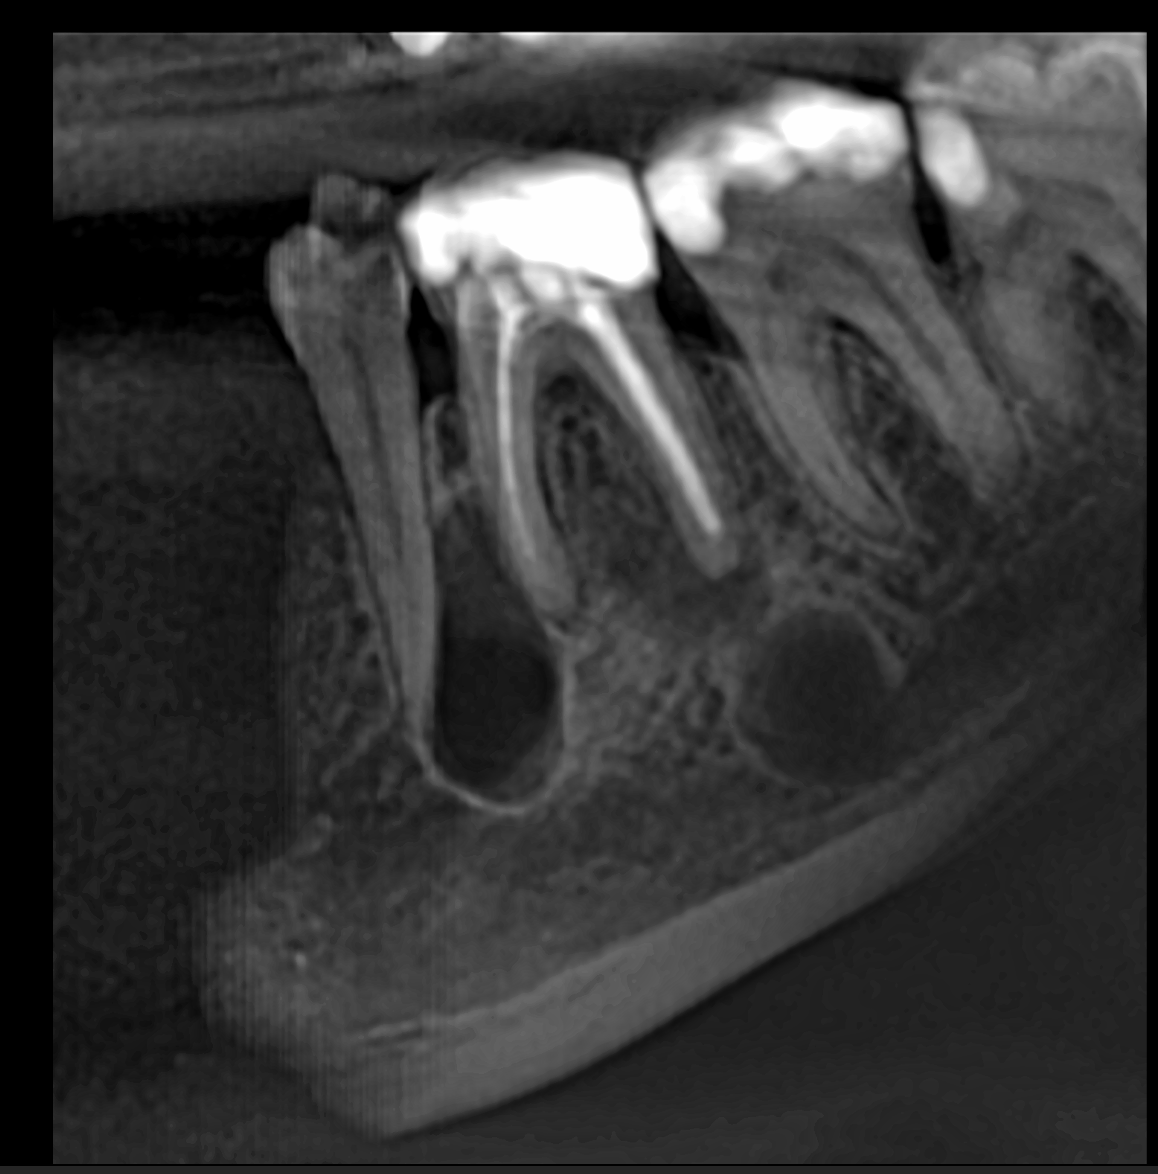

In this first case, the patient, who lived abroad and was unable to travel at the time, had swelling of her right mandible (Fig. 6), had had breast cancer and had been under bisphosphonate treatment for 18 months. She sent a panoramic radiograph (Fig. 7), and this showed a minor apical infection of the mandibular right first molar, which had undergone endodontic treatment. A CBCT scan was then taken, and from examining her scan, we could clearly see an area of bone densification (Fig. 8). This should be a red flag because this indicates the start of bone necrosis.

7: Panoramic radiograph showing a minor apical infection of the mandibular right first molar and endodontic treatment.

Fig. 8: Axial view of the CBCT scan showing a small apical infection of the mandibular right first molar, surrounded by an area of dense ossification extending over a large part of her mandible.